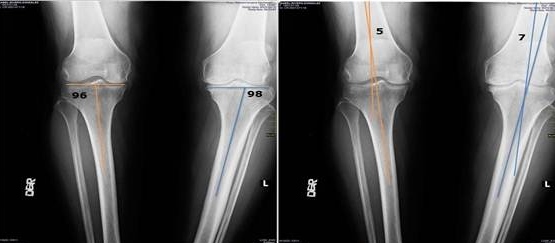

Antes

Después